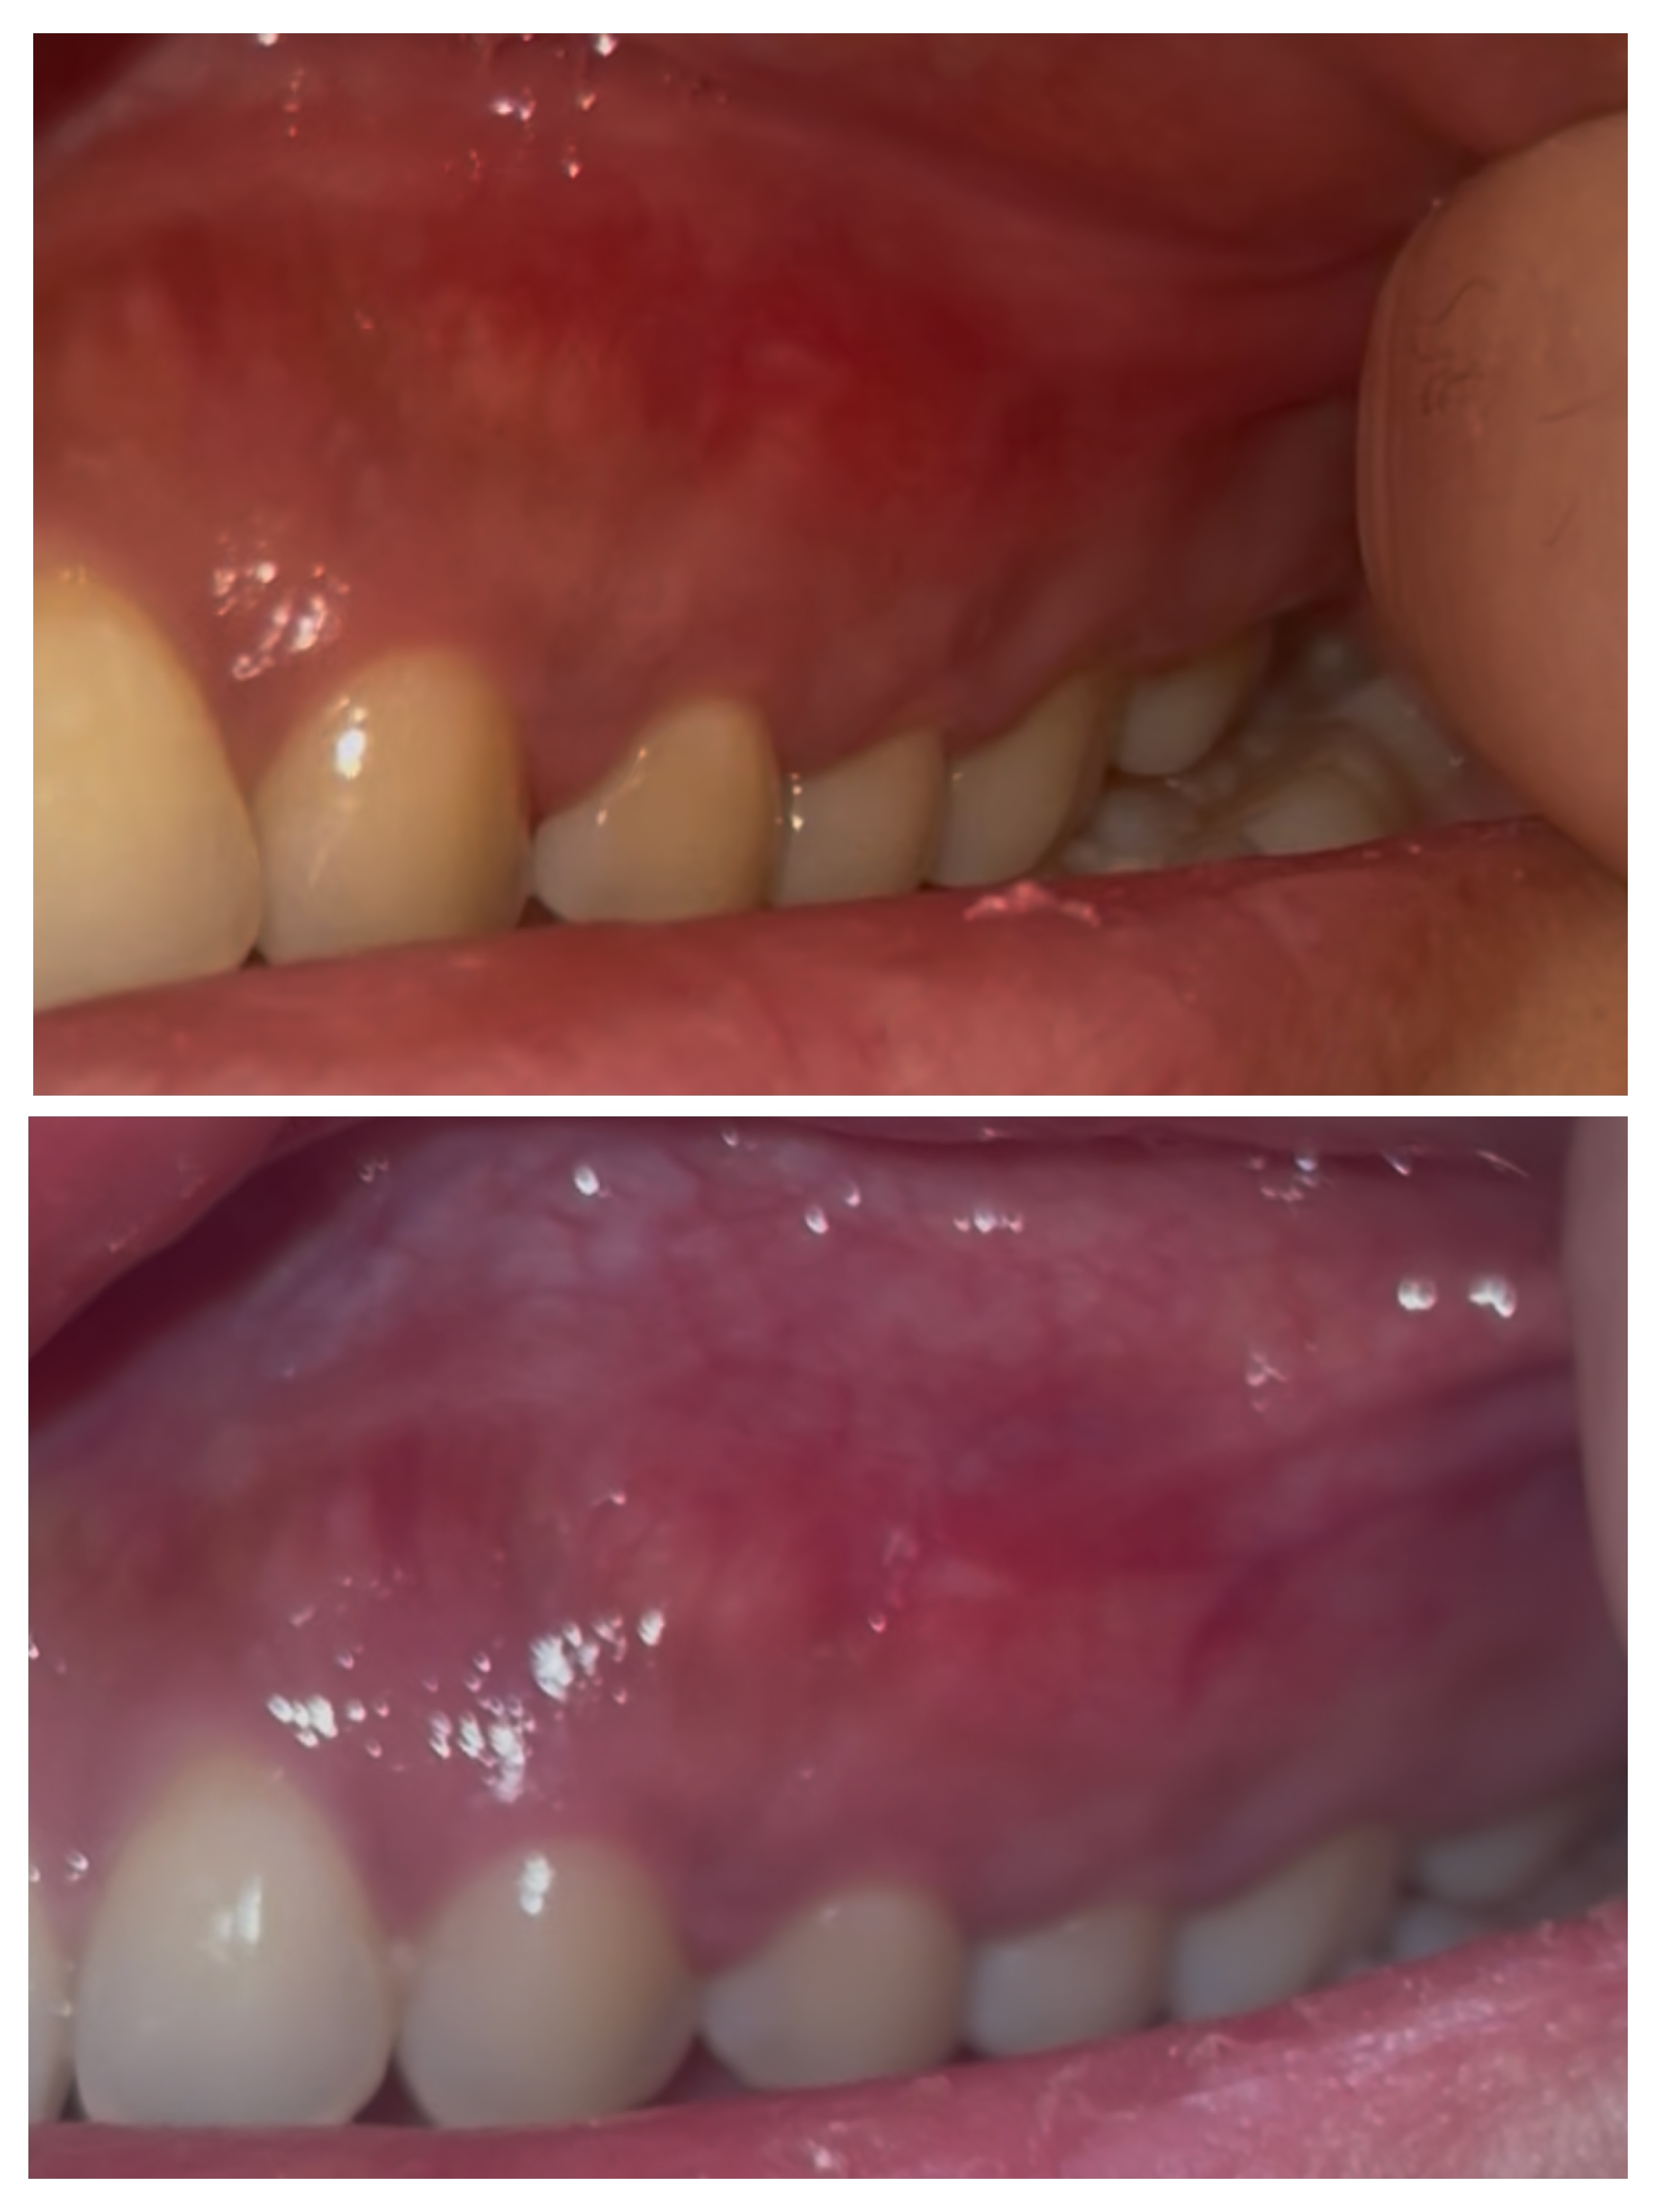

気付いたのは昨日ですが、前歯の歯茎に赤みがあります

コウハンショウ、もしくは癌の可能性はありますか?

うえの写真が昨日で下の写真が本日です

画像10F7E211D-4710-4E2D-B10E-22133D0D5FD7-COLLAGE.jpeg